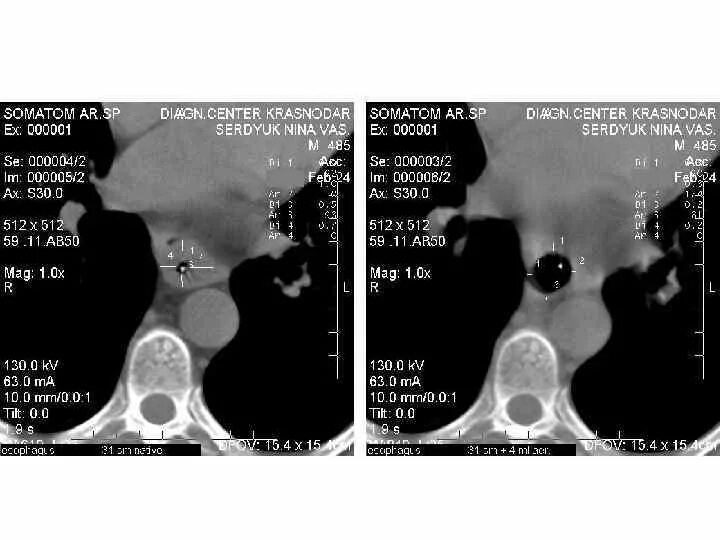

Ожог верхних дыхательных путей соответствует